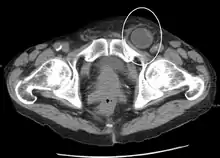

In the diagnosis of abdominal hernias, imaging is the principal means of detecting internal diaphragmatic and other nonpalpable or unsuspected hernias. Multidetector CT (MDCT) can show with precision the anatomic site of the hernia sac, the contents of the sac, and any complications. MDCT also offers clear detail of the abdominal wall allowing wall hernias to be identified accurately.[13]